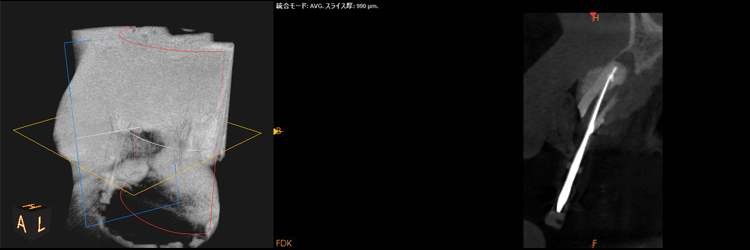

超最難関case(根尖病巣+パーフォレーション(術者のミス)

通常は「抜歯が当然」のcaseですが抜歯なしで治療成功事例

右下の画像が一番変化を診る上で基準となる画像でして(CT)、根の先端の病気が減っていること、白く濃く映った根のお薬がしっかりと入っている事が分かると思います。根の途中の黒い穴は、最初のドクターが謝って穴をあけてし合った後です。こういった高度な治療もセカンドオピニオンとしてお受けしております。

治療前

治療中

治療1年後

治療後3年後

レントゲンで施術前と施術後の比較

・赤色の部分→ドクターのミスをした箇所になります「パーフォレーション」

→結果、、、そこから病気ができています。。。

→通常はこれだけで「抜歯」となります。。。

・黄色の部分が根尖の病巣です。

→この原因でも抜歯となることもあります。

こちらの症例に関しても抜歯するくこともなく、治療成功となります。